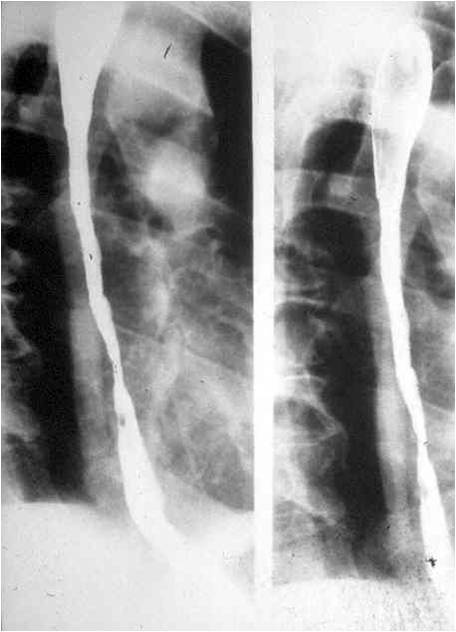

Esophageal stenosis:

Frequently, it is a complication of esophageal inflammation, which causes narrowing of the esophageal lumen. The degree of narrowing can be so severe that the lumen almost completely obliterated by scarring. It may also occur due to corrosive effect of acid or alkali indigestion as well as in reflux disease or precipitated by long term duodenal tube placement. Irritation of the esophageal mucosa causes inflammation. Alkali indigestion usually results in more severe injury as it causes colliquative necrosis in the deep wall layers, while after acid indigestion the mucosal surface is covered with a fibrotic crust which prevents deeper penetration of the corrosive agent. In addition to the stricture inflammatory diseases are also complicated by esophageal shortening, thus part of the fornix is pulled up into the mediastinum. Frequently, in patients with reflux esophagitis the stricture only involves the cardia sparing the esophagus; still a shortened esophagus could be detected.

Image

Fig.4.: Esophageal stenosis

Radiographic findings: A long segment, sharp contoured esophageal stricture is detected. Due to stiffness of the fibrotic wall no peristaltic activity can be seen. Differentiation from tumors can be difficult, thus patient history is important. Tumors cause slowly progressing dysphagia, but generally involve shorter segments.